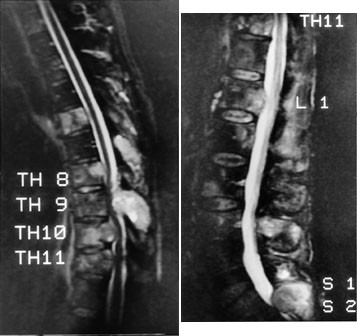

Ved truende og manifeste tverrsnittslesjoner hos kreftpasienter vil årsaken oftest være skjelettmetastaser med omgivende intraspinal, ekstradural bløtdelstumor som komprimerer medulla. Minst 20 % av pasientene vil ha medullakompresjon på mer enn ett sted (6). Hele columna bør undersøkes. MR viser både metastasene og medullakompresjonen, og MR-undersøkelse er den beste metoden til å utrede disse pasientene. Sagittale T1-sekvenser og STIR- eller T2-sekvenser gir god oversikt over medulla (fig 2), og kan eventuelt suppleres med aksiale snitt svarende til medullakompresjonen. I en artikkel i Tidsskriftet har Brenne og medarbeidere gitt en utførlig omtale av medullakompresjon ved metastatisk kreftsykdom (7). Vi slutter oss til det syn at utredningen bør skje raskt, ved hjelp av MR. Det er viktig å være oppmerksom på at de aller fleste pasienter med medullakompresjon har hatt utstrålende radikulære smerter i nivå for kompresjonen i forkant av de nevrologiske utfall.

Dersom man ikke kan påvise noen medullakompresjon som årsak til de nevrologiske utfall, må undersøkelsen suppleres med intravenøs kontrast (gadolinium). Postkontrastseriene vil i slike tilfeller oftest avsløre tumorutsæd i meninger eller tumor i medulla (fig 3).